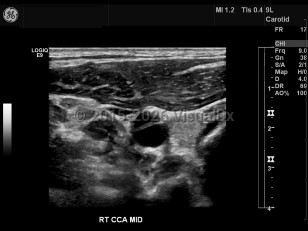

Carotid artery dissection

Carotid artery dissection is tearing of the carotid artery wall between the intimal and medial layers, resulting in an abnormal collection of blood or intramural hematoma. May compromise the arterial blood flow, causing ischemic stroke. Painful condition. Characteristic findings include headache and/or neck pain on the side of the dissection, periorbital headache / pain, miosis, ptosis, amaurosis fugax, tinnitus, facial numbness, dysgeusia, tongue paresis, and syncope. Caused by a weakness in the arterial wall. Sometimes the result of blunt trauma to the neck or head as a result of a sports injury, strenuous exercise, whiplash, childbirth, or sexual intercourse. Certain conditions may compromise the strength of the arterial wall, including Marfan syndrome, fibromuscular dysplasia, atherosclerosis, Ehlers-Danlos syndrome type 4, and homocystinuria.

Initial treatment is typically anti-coagulation therapy.